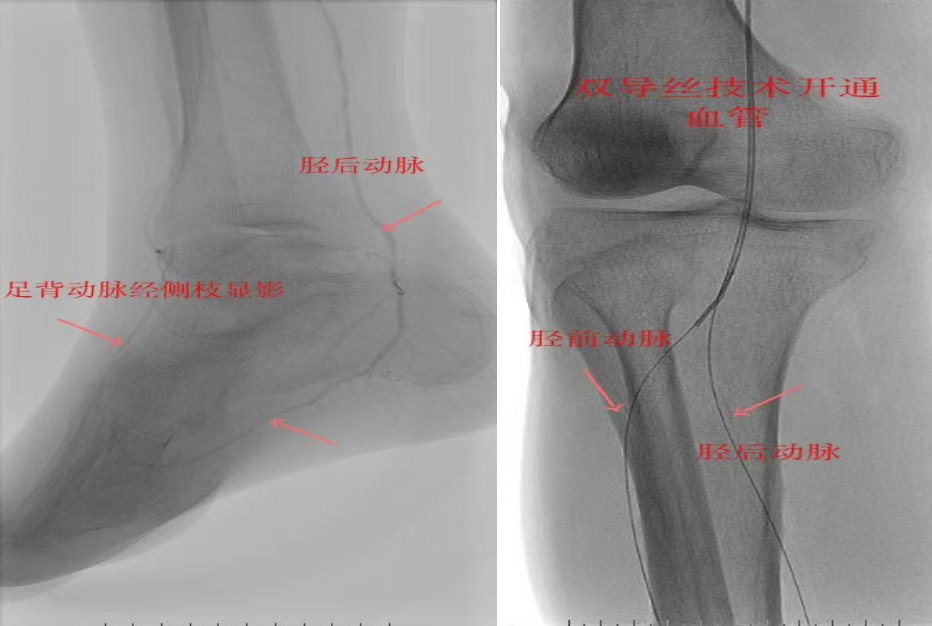

67岁女性患者,多年糖尿病、冠心病史,因右足溃烂伴凉麻疼痛长达2年就诊,此前曾接受外院介入术后血管再度闭塞。此次检查发现其股浅动脉、腘动脉至膝下血管全程闭塞,且伴有严重钙化。团队迎难而上,创新性经足背动脉逆向穿刺,耗时3小时成功贯通胫前动脉。术后当夜患者足部即感回暖,溃烂足趾疼痛显著缓解。术后结合中药外治(换药、熏洗、去腐生肌膏外敷)加速创面愈合。该患者已于出院,院外换药治疗。

影像检查:股浅动脉、腘动脉至膝下血管全程闭塞伴严重钙化。

两例患者共同凸显三大高难度治疗挑战:1.患者高龄且基础病复杂;2.血管全程多节段闭塞、钙化程度严重;3.常规顺向开通路径已被完全阻断。团队果断采用远端逆行穿刺技术,在纤细的足踝部血管建立治疗通道,实现“逆向破冰”。